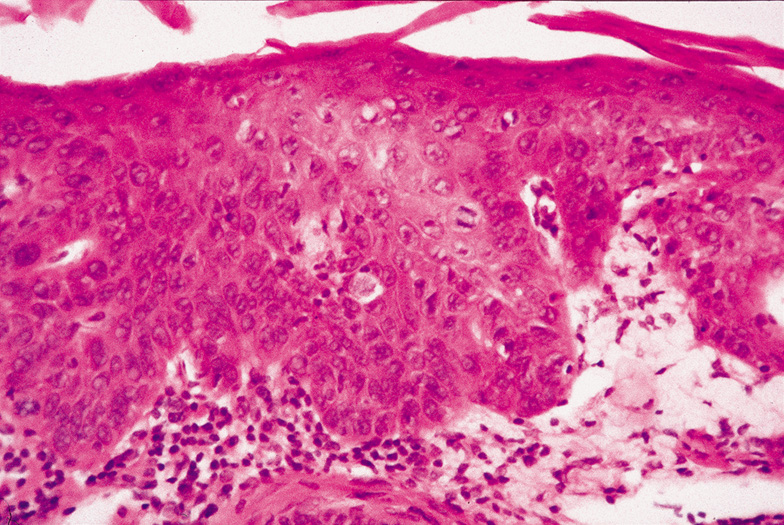

Lesions of molluscum contagiosum often affect the periorbital and lid skin as 1- to 3-mm domeshaped papules with a small central dell. This large pox virus multiplies in the cytoplasm, and, histologically, homogeneous purple intracytoplasmic inclusion bodies (molluscum bodies) are seen in an acanthotic epidermis (see Fig. 7).

Fig. 7. Molluscum Contagiosum—A. Umbilicated lesions typical of molluscum contagiosum on the upper lid of a child. Infection near the edge of the lid may cause a toxic follicular conjunctivitis. B. Low-power photomicrograph demonstrating crater shape of excised lesion (hematoxylin and eosin stain). C. High-power photomicrograph illustrating the large clumps of eosinophilic viral inclusions in the epithelial cells (“molluscum bodies“) (hematoxylin and eosin stain). (Photos courtesy of William Morris, M.D.)